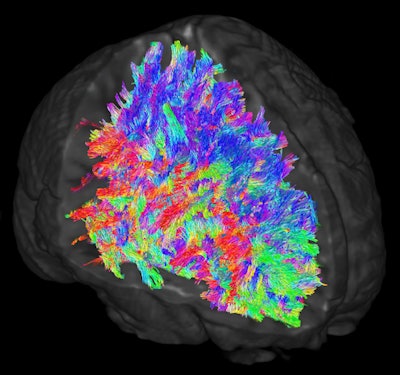

Images illustrate white-matter tracts estimated through DWI-MRI and tractography. Wiring patterns within the brain are thought to vary across individuals. The colors represent the directions of the white-matter tracts.In addition, the connectome-level analysis of white-matter structural connectivity revealed a significant increase in the SSRI-exposed group between the right amygdala and the right insula (Cohen d = 0.99), compared with the healthy controls and babies whose mothers were not treated for depression (p < 0.05).